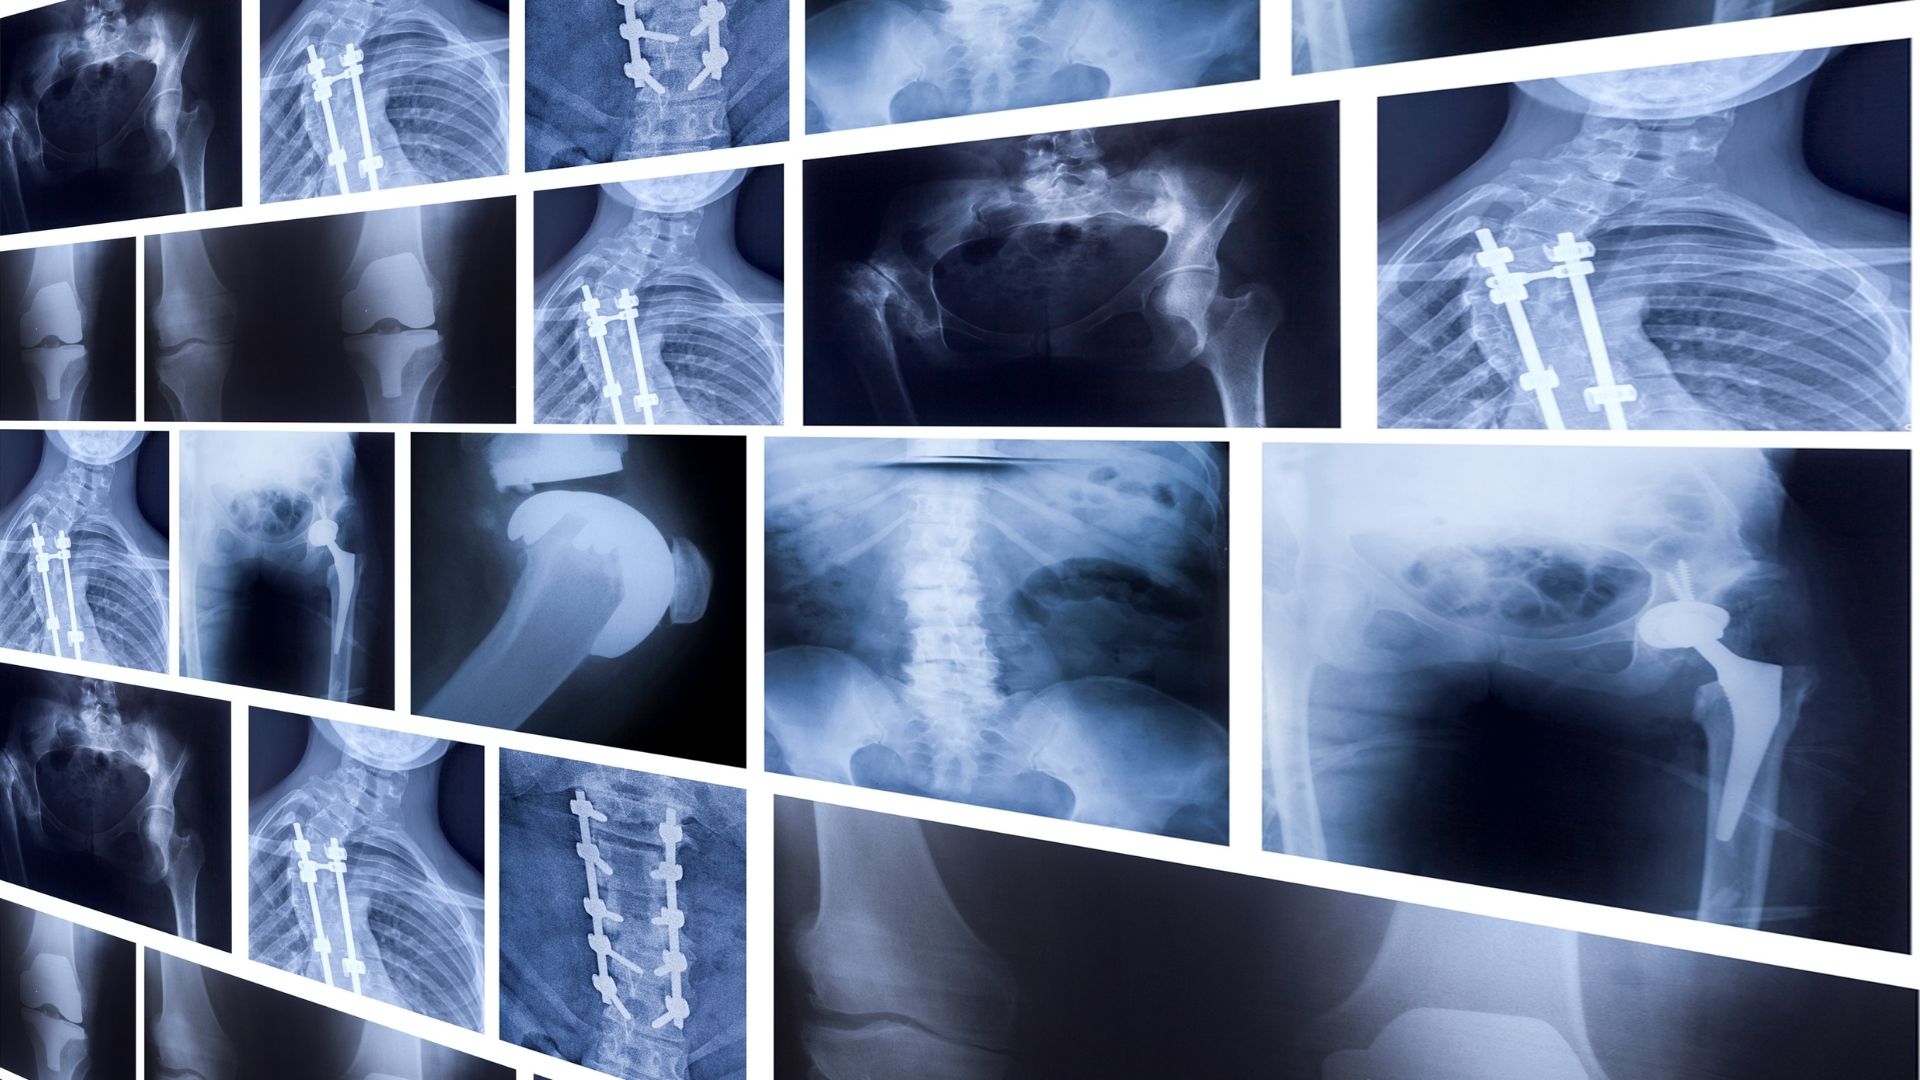

Chụp X-quang là kỹ thuật chẩn đoán hình ảnh sử dụng tia X để tạo ra hình ảnh cấu trúc bên trong cơ thể, đặc biệt là hệ xương và một số cơ quan nội tạng. Đây là một trong những phương pháp được áp dụng sớm và phổ biến nhất trong y học.

Về nguyên lý, tia X là một dạng bức xạ có khả năng xuyên qua cơ thể người. Khi tia X đi qua các mô với mật độ khác nhau, mức độ hấp thụ tia cũng khác nhau. Xương có mật độ cao sẽ hấp thụ nhiều tia X hơn nên hiện lên màu sáng trên phim, trong khi các mô mềm hấp thụ ít hơn và hiện màu tối hơn. Nhờ sự khác biệt này, bác sĩ có thể quan sát và đánh giá tình trạng bên trong cơ thể.

Trong thực hành y khoa, chụp X-quang đóng vai trò quan trọng trong nhiều lĩnh vực. Đây là phương pháp hỗ trợ bác sĩ phát hiện nhanh các tổn thương xương khớp, đánh giá tình trạng phổi, kiểm tra răng hàm mặt và theo dõi tiến triển của một số bệnh lý. Với ưu điểm thao tác đơn giản, thời gian thực hiện ngắn và khả năng cung cấp thông tin ban đầu nhanh chóng, X-quang thường là lựa chọn đầu tay trong quá trình thăm khám.

Chụp X-quang được sử dụng phổ biến nhất trong lĩnh vực xương khớp và chấn thương. Phim X-quang giúp phát hiện gãy xương, nứt xương, trật khớp hoặc các biến dạng xương sau tai nạn và va chạm. Ngoài ra, phương pháp này còn hỗ trợ theo dõi quá trình liền xương trong điều trị.

Bên cạnh chấn thương cấp tính, X-quang cũng giúp đánh giá các bệnh lý mạn tính như thoái hóa khớp, loãng xương, cong vẹo cột sống. Hình ảnh X-quang cho phép bác sĩ quan sát mức độ hẹp khe khớp, thay đổi cấu trúc xương và các dấu hiệu tổn thương lâu dài, từ đó đưa ra hướng điều trị phù hợp.